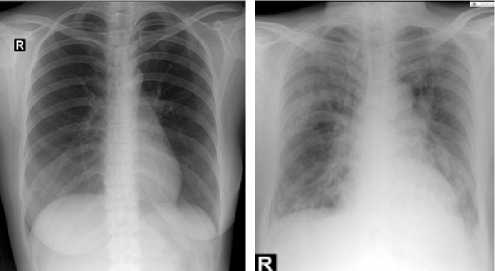

Citra rontgen thorax normal memiliki bentuk dan gambar yang cukup jelas pada rongga dada, sehingga terlihat mana yang merupakan paru-paru, jantung dan diafragma. Sedangkan pada citra rontgen thorax tidak normal memiliki beberapa kelainan pada bagian dari rongga paru-paru, seperti pada apex terdapat bercak bercak putih, sudut carina berada diluar batas normal, sinus prenicocostalis yang tidak tajam serta terkadang terlihat jelas adanya bercak putih pada rongga paru paru karena terdapatnya cairan pada paru paru. Berikut merupakan contoh citra yang digunakan dalam penelitian

Gambar 3 : Contoh citra thorax normal (kiri) dan tidak normal (kanan)